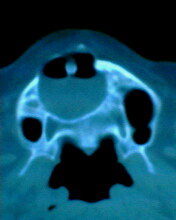

患者:男71岁,右侧上颚肿物无痛性生长7年.

右上颌骨近中线部见类圆形低密度区,上方见一液平,周围见一薄硬化环,前下方见一牙根,后方累及水平板。上方突入鼻腔前下部,下方突入口腔。

考虑:右侧上颌骨囊肿伴感染。